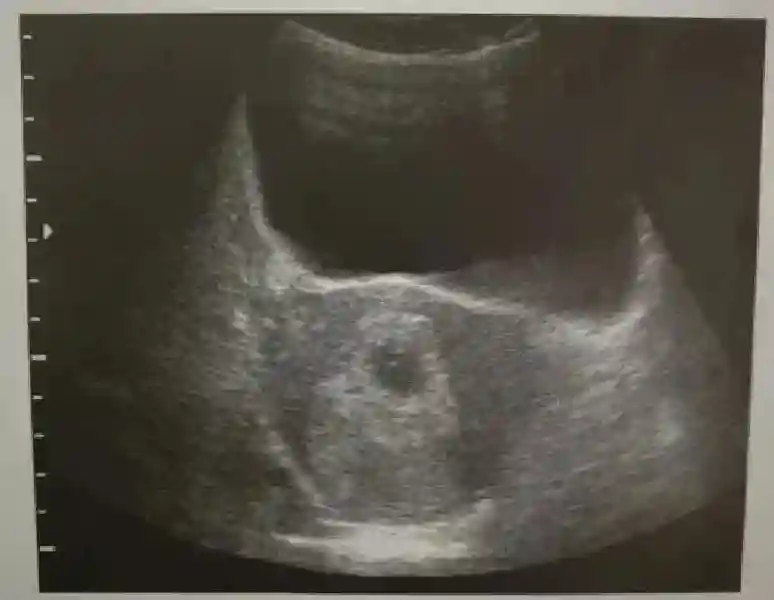

1??妊娠囊:早期妊娠囊:正常妊娠囊位于宫腔上段,表现为宫腔内圆形或椭圆形的无回声区,周边为完整的、厚度均匀的强回声环,强回声环厚度≥2mm,强回声是妊娠绒毛的回声,随着妊娠囊的增大,形成特征性的“双环征” ,10周以后消失。正常的妊娠囊增长速度是平均 1 mm /d。